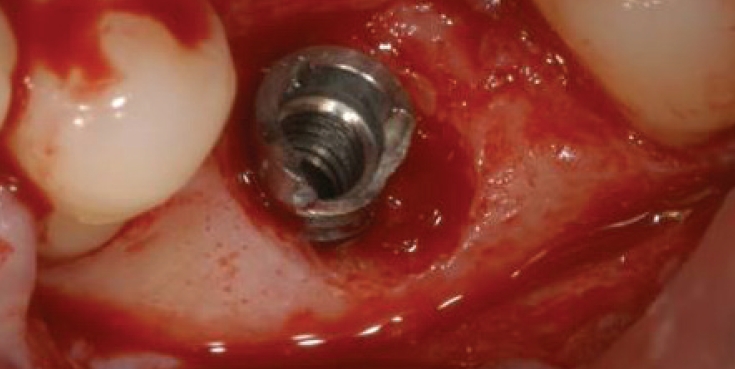

1) 보철물연결나사 제거

임플란트연결나사는 보통 30N으로 채결되어 구강내에서 오랜기간을 유지하게 되는데 사용기간동안 반복되는 진동으로 풀리는 경우가 생길 수 있다. 이런 경우에는 보촐물의 동요도를 인지하게 되는데 서둘러서 치과를 방문하여 다시 조여주면 큰 문제가 없지만 방치하게 되면 피로파절이 발생하게 된다. 이때는 일단 먼저 보철물을 먼저 제거하고 파절된 나사를 제거하면 된다. 연결나사는 초음파기구로 역회전을 주면서 돌리면 조금씩 밀려나오게 되는데(Fig. 3) 이때 곧게 핀 익스플로러를 이용할 수도 있다(Fig. 4).

Fig. 3.

파절된 연결나사를 초음파기구로 역회전하면서 제거하기

jkda-2026-64-2-006f3.jpg